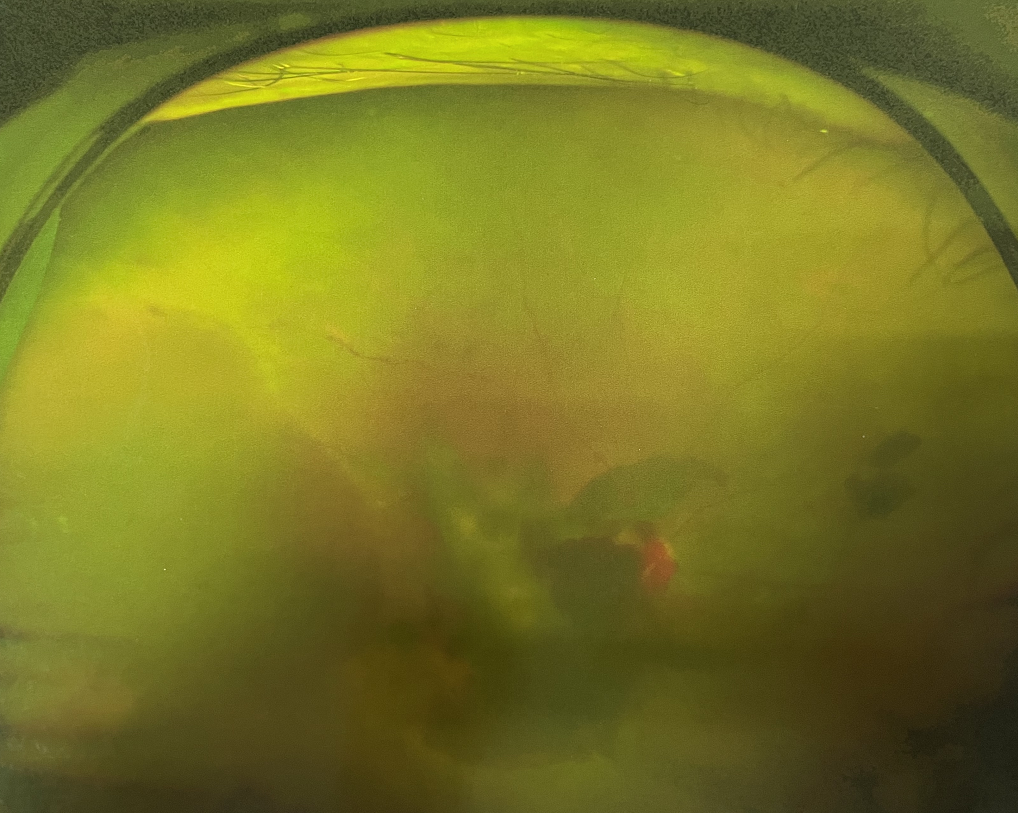

糖尿病視網(wǎng)膜病變能治愈嗎?

【文章導(dǎo)讀】糖尿病視網(wǎng)膜病變是糖尿病在眼部的主要并發(fā)癥,是我國(guó)四大致盲眼病之一,主要以視網(wǎng)膜血管改變?yōu)椴±硖卣鳌Q鄣锥啾憩F(xiàn)為視網(wǎng)膜出血、滲出、新生血管及增殖膜形成,嚴(yán)重威脅患者

糖尿病視網(wǎng)膜病變是糖尿病在眼部的主要并發(fā)癥,是我國(guó)四大致盲眼病之一,主要以視網(wǎng)膜血管改變?yōu)椴±硖卣鳌Q鄣锥啾憩F(xiàn)為視網(wǎng)膜出血、滲出、新生血管及增殖膜形成,嚴(yán)重威脅患者的視覺健康。

糖尿病視網(wǎng)膜病變

糖尿病視網(wǎng)膜病變可分為六期:

Ⅰ期:有微血管瘤或并有小出血點(diǎn)。

?、蚱冢河悬S白色“硬性滲出”或并有出血斑。

?、笃冢河邪咨?ldquo;軟性滲出”或并有出血斑。

?、羝冢貉鄣子行律芑虿⒂胁Aw積血。

?、跗冢貉鄣子行律芑虿⒂欣w維膜增生。

?、銎冢貉鄣子行律芑虿⒂欣w維膜增生,并發(fā)視網(wǎng)膜脫離。